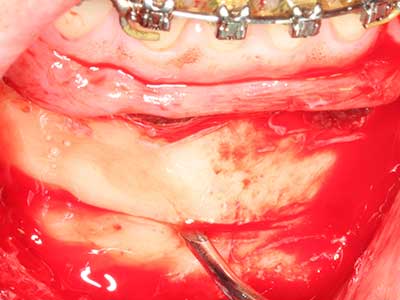

Autologous bone transplants are used in the form of blocks, shells, rings and are also combined with bone replacement materials as chips. If the implant site is prepared at the same time as the augmentation, various bone filter systems have proven effective for collecting the resulting bone chips. As an alternative, the implant site can be prepared using a low-speed device without irrigation. If an implant is not inserted, bone chips can be harvested from the periphery with bone scrapers. This is also possible with piezosurgery using specialized attachments that yield higher-quality bone chips compared chips harvested with round drills, as has been confirmed in a study comparing the two methods (Chiriac, Herten et al. 2005).

Piezosurgery has additional advantages when harvesting bone blocks. In addition to the high precision with osteotomy described above, the use of the thin saw tips specifically minimizes loss of material. Greater loss of material during harvesting can be expected with the thicker instrument tips, particularly when using Lindemann drills (Lakshmiganthan, Gokulanathan et al. 2012). The basal separation, which is necessary particularly for retromolar block transplants, is simplified by specially designed rectangular saws, with the result that piezosurgery is viewed as a precise, simple and safe procedure for harvesting retromolar bone blocks (Happe 2007) (Fig. 1-12).